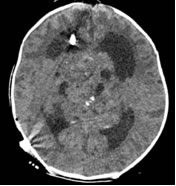

术后复查CT结果:分流管位置佳,肿瘤体积较5天前明显增大。